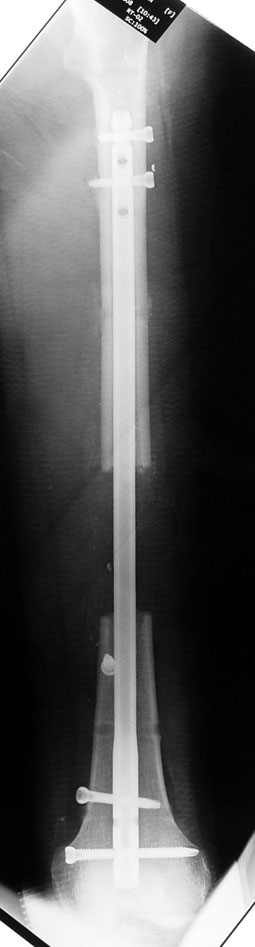

Installment of the intramedullary nail and osteotomy:

The patient lies is supine position at a traction table and legs are crossed with the uninvolved leg at the bottom. The medullary cavity is penetrated through piriform fossa using the standard method, and medulla is reamed 1.5 mm thicker than the nail to be used, over a guidewire. Proximal femur is reamed more, because the intramedullary nail is thicker proximally. The osteotomy site is planned at the X-Rays. It is important that at least 8 cm. of nail remains distal to the osteotomy site after the completion of the lengthening procedure. Percutaneous corticotomy is performed. The guide wire is advanced distally in order to measure the length of the nail. An intramedullary nail of apropriate length is placed. In the end, the nail is interlocked proximally, a suction drain is placed and the fist step of the operation is completed.

2. Step:

The application of the external fixator: Three Schanz screws are placed distally and three screws are placed proximally. At least 1 mm of distance shall remain between the screws and the nail.

In selected cases, we prefer to use a combination of a unilateral dynamic axial fixator and an interlocked intramedullary nail, in order to protect the length and alignment after the completion of the lengthening procedure. As a prerequisite for this technique, the narowest diameter of the medullary cavity shall be wider than 7 mm and the length of the nail segment distal to the osteotomy site shall be at least 8 cm. after the completion of the lengthening procedure.The intramedullary nail neutralizes shear and bending forces on femur during lengthening, shortens external fixation time, and protects newly formed bone against fractures. In our series, subtrochanteric osteotomy was performed in one case. No varus angulation occured despite the intramedullary nail.